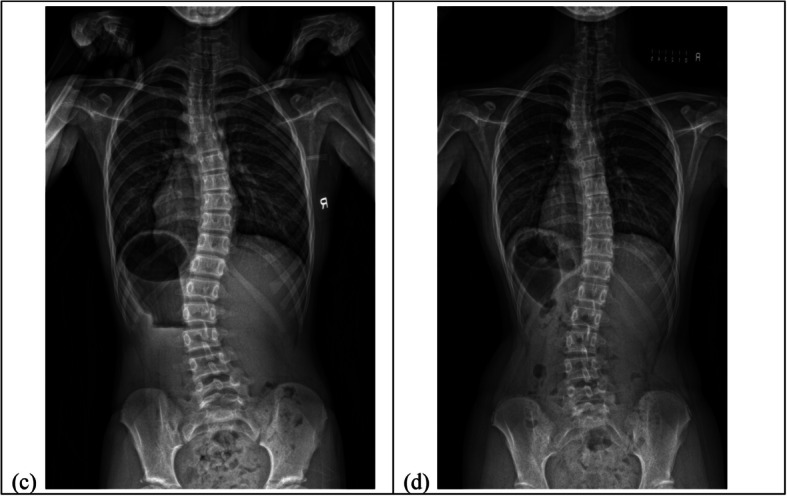

Background: Changes in coronal curve type and curve span may be linked to spinal and rib cage deformities. Therefore, it is crucial to comprehend the potential impact of these changes on brace treatment. This study aims to investigate the relationship between curve progression and change in coronal curve type and curve span in braced patients, and to compare the coronal balance and change in apical vertebral between patients with and without curve pattern change.

Methods: Two hundred seventeen patients who fulfilled the Scoliosis Research Society brace referral criteria were recruited. Radiographs at prebrace and brace weaning were assessed. Patients were classified into three groups based on the curve pattern at prebrace: major thoracic (MT), major lumbar (ML) and double major (DM). Change in coronal curve referred to curve of the greatest magnitude changes from thoracic to lumbar or vice versa. Change in curve span defined as change of at least two vertebral levels in the end vertebra of the curve. Change in apical vertebrae referred to change of at least one vertebral level. The association between coronal imbalance, major curve progression and regression, change in coronal curve type, change in curve span, change in apical vertebrae, and curve type were studied using Chi-square test. Multivariable logistic regression was used to predict curve progression at brace wean in each curve type.

Results: The major lumbar group exhibited a higher risk of coronal imbalance (Listing-MT: 5.6% vs ML: 37.7% vs DM: 23.5%, p < 0.001 and truncal shift-MT: 6.9% vs ML: 27.3% vs DM: 2.9%, p < 0.001) and changes in apical vertebrae (MT: 30.6% vs ML: 58.4% vs DM: 45.6%, p = 0.003). The double major group had a greater likelihood of experiencing changes in the coronal curve type (MT: 0% vs ML: 15.6% vs DM: 25%, p < 0.001) and major curve progression (MT: 23.6% vs ML: 22.1% vs DM: 52.9%, p < 0.001). In the major thoracic group, predictive factors for curve progression included being female, having poor brace compliance, and no change in curve span. However, no significant relationships were found for the major lumbar group. Patients with a larger prebrace major Cobb angle, larger thoracic kyphosis and poor brace compliance from double major group were more likely to experience curve progression.

Conclusions: This study suggests that each curve type undergoes distinct changes during bracing. Future studies should consider the influence of curve type in study design and address the challenges associated with each type.